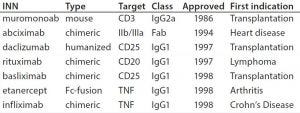

Table 1: Some of the first approved chimeric and humanized antibodies

Increasing Number of Monoclonal Antibody Approvals

By the 1990s, we had taken about 20 different MAbs from our research laboratory into the clinic. In 1997 and 1998, several chimeric and the first humanized antibodies were approved (Table 1). Campath-1H was approved in 2001, shortly followed by Humira™ (adalimumab). So far, the year 2017 appears to be setting a record in MAb approvals, with about eight approvals so far and perhaps more by year end (Figure 5).